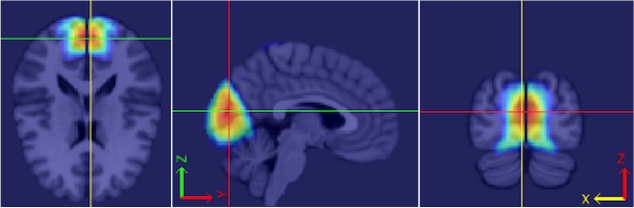

Our procedure is as follows. Each fMRI scan was separated into left and right hemispheres. Thus, each hemisphere contained voxels. Similar to standard group ICA (Calhoun et al., 2001b), a dimension reduction using PCA was applied to each hemisphere of each subject. 15 PCs are obtained for each hemisphere. A group data matrix was generated by concatenating the reduced data of both hemispheres of the 20 subjects in the temporal domain. Thus, the aggregated matrix has dimension , where , , and . Our algorithm of homotopic group ICA is then applied on this matrix. Fifteen estimated independent components are postulated by H-gICA. As shown in Figure 12, out of the 15 components, several brain networks were found including: the visual network 12, the default mode network 12, the auditory network 12, and the motor network 12. Compared with the ICs obtained from ordinary gICA, shown in 12, 12, 12 and 12, H-gICA improves the estimation of all of these sources by yielding substantially more clearly delineated networks.

The approach of H-gICA also allows us to calculate the brain functional homotopy of each brain network. To compare the brain functional homotopy of ADHD and typical developed children, we choose 20 ADHD subjects and 20 subject-macthed controls. The subjects and controls were matched in gender and age. Via Equations (4) and (5), the estimated functional homotopy of four networks (visual, default mode, auditory and motor) are shown in Figure 13. As we can see, the functional homotopy of ADHD children tends to be lower in both visual networks and the auditory network. These represent meaningful leads on the exploration of homotopic network relationships and disease, though we leave a full exploration to later work.

In this paper we present a new group ICA method called homotopic group ICA (H-gICA). Similar with ordinary group ICA methods, H-gICA can analyze data for multiple subjects and estimate common underlying IC’s across individuals. By concatenating the fMRI data of the two hemispheres, H-gICA effectively doubles the sample size. It improves the power of finding the underlying brain networks by rearranging the data structure and utilizing the known information of synchrony between bi-laterally symmetrically opposing inter-hemispheric regions. Both the simulation study and the application on ADHD 200 data show that H-gICA is preferable to ordinary gICA when the data are homotopic, increasingly so as noise increases. Moreover, H-gICA remains preferable to gICA at estimating homotopic sources, even in the presence of non-homotopic sources. Effectiveness was demonstrated by application on the ADHD-200 dataset. Several brain networks were found and clearly represented in smoother, more clearly delineated, contiguous volumes than ordinary gICA. The main networks found included visual networks, the default mode network, the auditory network, as well as others. Moreover H-gICA enables certain measurement of the functional homotopy of the underlying functional networks. This potentially offers the opportunity to analyze the relation of the brain functional homotopy between the left and right hemisphere of the brain with diseases.